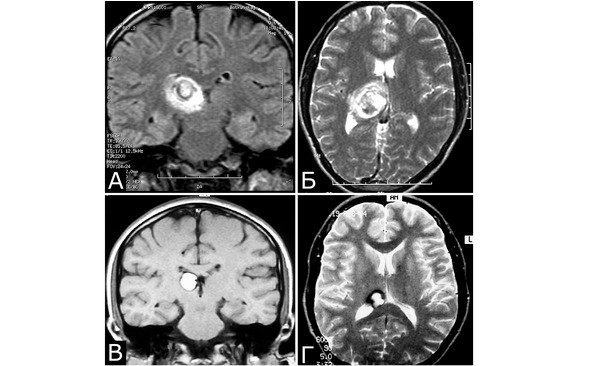

Рис. 29.I. Изменение размеров кавернозных мальформаций. КМ задних отделов зрительного бугра справа. А, Б – МРТ на 10-е сутки после острого развития общемозговых и очаговых симптомов (режимы Т1, Т2, фронтальная и аксиальная проекции). В, Г – МРТ через 1,5 г от начала заболевания. Неврологическая симптоматика полностью регрессировала. Объем КМ уменьшился (режимы Т1, Т2, фронтальная и аксиальная проекции)